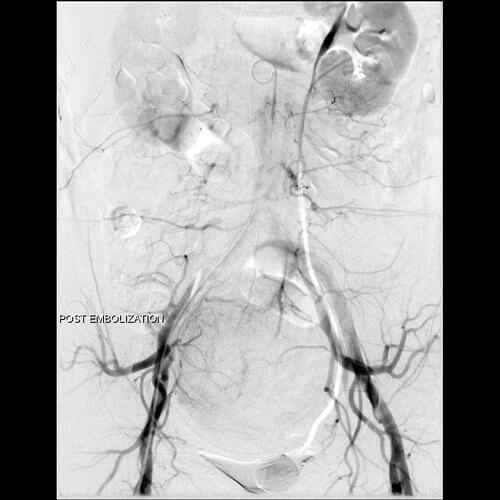

42 year old female who presents with abnormal bleeding, menstrual cramping, and frequent urination and subsequently undergoes UFE.

42 year old female who presents with abnormal bleeding, menstrual cramping, and frequent urination and subsequently undergoes UFE.